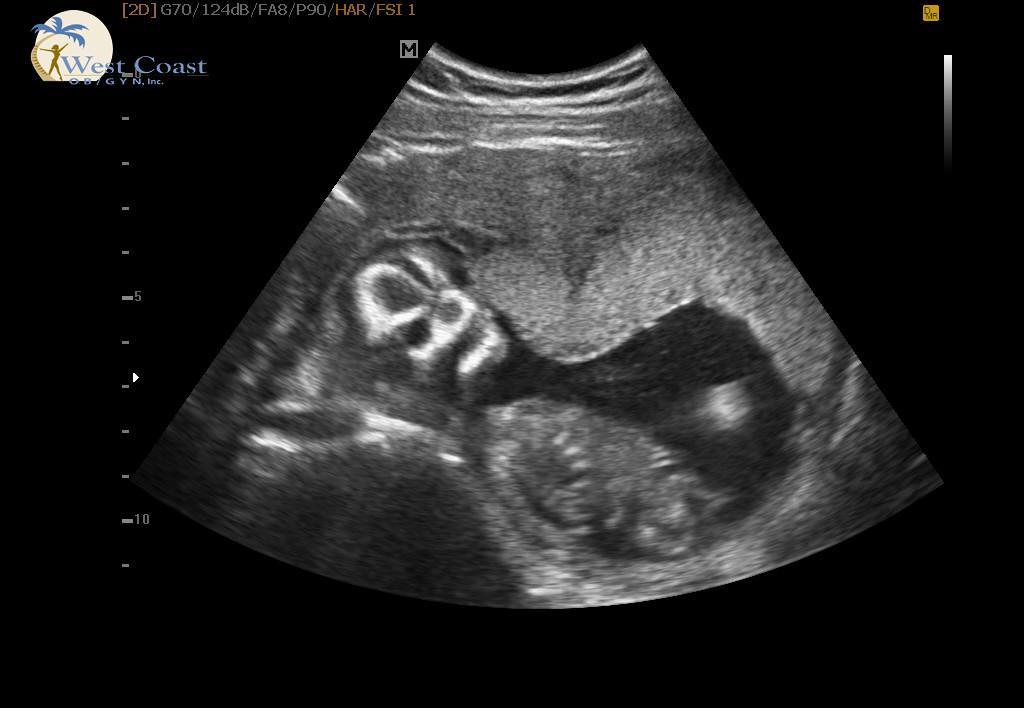

Had my ultrasound today!! Haven't seen the baby since 10 weeks. I am 18w2d. I'm jealous of the profile shots I've seen on here.. This is definitely our baby and is stubborn like us!! Lol the tech tried everything to get it to flip over since it was laying face down. Oh well! Everything looked great, heartbeat was 139 and my due date is still June 6th. She could tell the gender but we had her write it in an envelope and we have the gender reveal on Saturday.